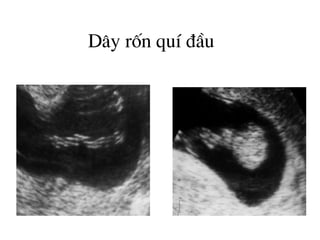

D©y rèn quÝ ®Çu

D©y rèn

H×nh ¶nh cña d©y rèn